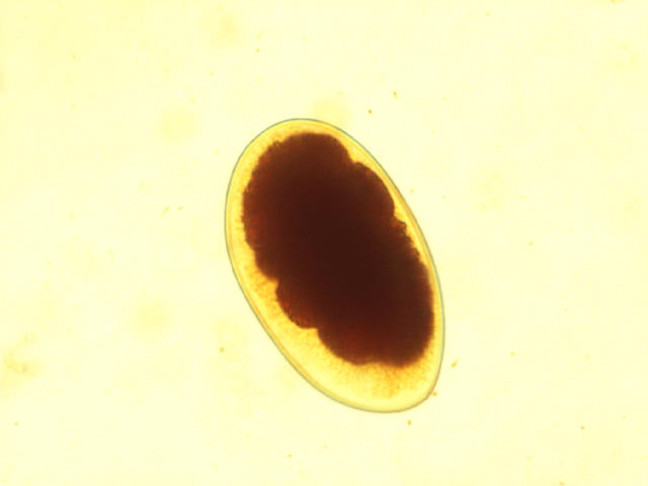

Enterobius Vermicularis

- 10x

Enterobius 10x

Notice the flat edge